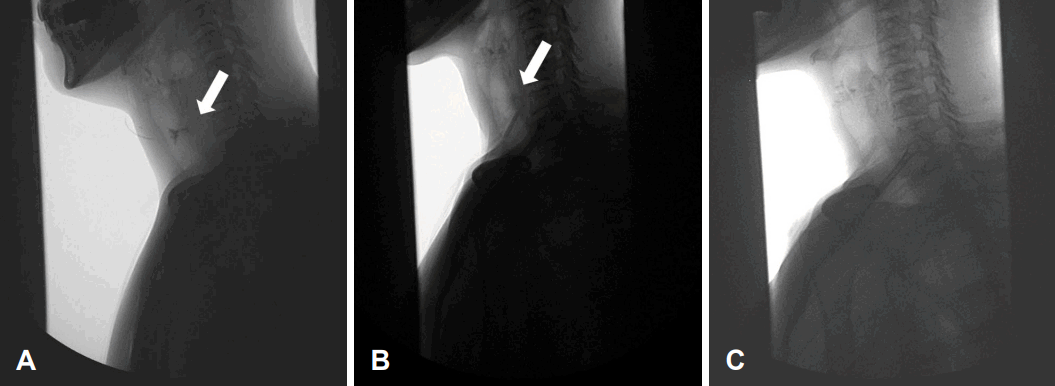

Endoscopic and surgical findings. A: No clear evidence of perforation and inflammation under laryngoscopy. B: Perforation at the right postcricoid area (arrowhead), upper esophageal sphincter (arrow). C: Transoral repair of hypopharynx perforation after mucosal trimming. D: Reinforcement of the hypopharynx perforation site using the sternocleidomastoid muscle rotational flap (arrow).

A 55-year-old female received EGD for dyspepsia. During EGD under sedation, there was excessive resistance felt in the endoscope as it passed through the upper esophageal sphincter area. As a result, the endoscope could not pass through the upper esophageal sphincter and the procedure failed. She was admitted to the hospital with persistent neck pain. Laryngoscopic findings revealed no evidence of perforation or inflammation (Fig. 1A).

An endoscopic evaluation under general anesthesia was done to find and treat the perforation. We found the perforation in the right postcricoid area, which was repaired with mucosal trimming and suture through transoral route (Fig. 1B and C).

Subsequently, a cervical incision was made to explore the site of the perforation bed. The area where the perforation had occurred was filled with granulation tissue. We removed the granulation tissue and cleansed the area with extensive irrigation. The hypopharynx perforation site was then reinforced using a sternocleidomastoid muscle rotational flap (Fig, 1D). The sternocleidomastoid muscle was resected in the inferior portion and was rotated superiorly based. The resected part of sternocleidomastoid muscle was anchored to the postcricoid area.